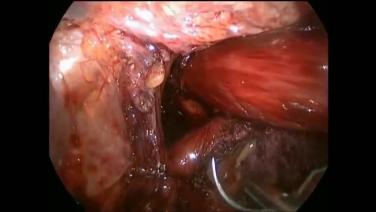

Large Hiatal Hernia Repair Using LINX with John Lipham, MD